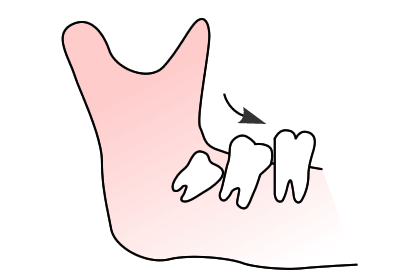

1問診、視診とレントゲン、CTにより親知らずの状態を確認します。

2上顎の場合は上顎洞との位置関係、下顎の場合は下顎管という神経との位置関係などを診査します。

3以上の検査を踏まえた口腔内の状況をご説明し、患者様の同意を得た上で抜歯します。

※親知らずを診査した上で、病院歯科での抜歯が適切と判断した場合は、福岡大学、福岡歯科大学などに紹介させていただきます。